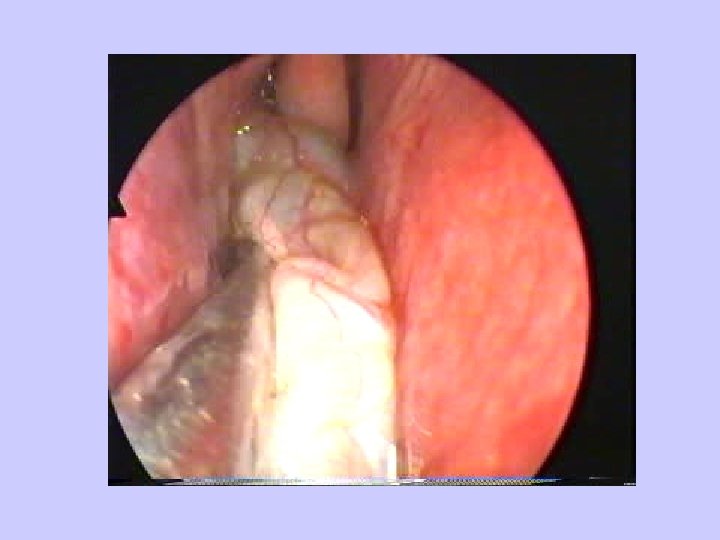

Antrochoanal polyp

Antrochoanal polyp